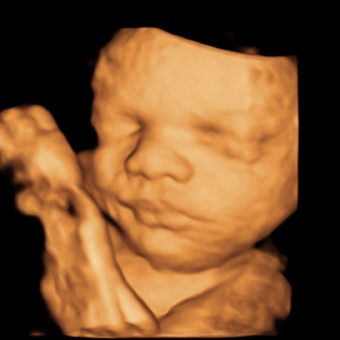

Baby Boy Brickhouse's Registry

Skylar & Briar Brickhouse

Lebanon, TN

March 17, 2026